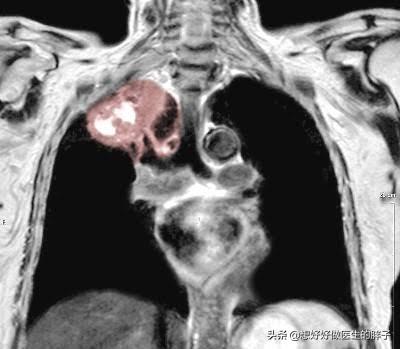

Ce qui précède est une brève introduction au diagnostic et au traitement des maladies qui excluent l'infarctus du myocarde ou la douleur à l'épaule gauche induite par l'angine. Si vous avez encore d'autres doutes, vous pouvez laisser un message ci-dessous, nous pourrons en discuter ensemble, mais nous devons également prendre en compte certains cas peu courants, comme la cause de la douleur à l'épaule gauche, il peut s'agir du côté gauche du cancer du poumon, qui est le plus souvent observé dans un cancer relativement rare, nous l'appelonsCancer du sillon pulmonaire supérieur (5 % des cancers du poumon)Lorsque la tumeur traverse la surface des poumons et irrite la paroi thoracique, elle provoque des douleurs à l'épaule et au dos. Des données montrent que le premier symptôme de douleur à l'épaule est le premier symptôme de près de 16 % des patients atteints d'un cancer du poumon suprasellaire.